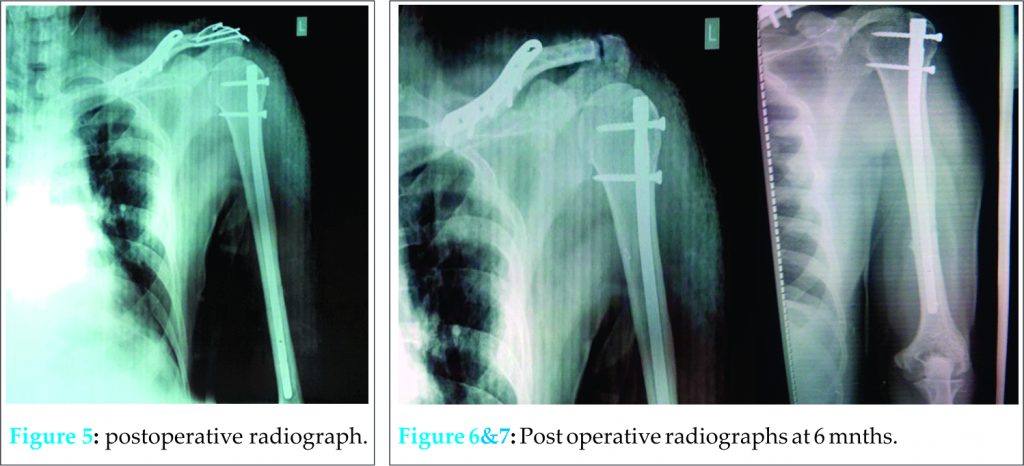

Postoperatively, arm pouch was given and three week immobilization was advised [Fig. 5]. Pendulum exercises were started at three weeks. At six weeks the Kirschners wires were removed and gentle passive range of motion exercises were started followed by active range of motion exercises as per pain tolerance of the patient. At three months, signs of union of humerus and clavicle were seen on radiographs and reduction of the AC joint was maintained with no postoperative complications. Patient was able to resume his daily activities with no tenderness at any fracture sites. At six months, union was radiologically complete [Fig. 6, 7] and patient was able to do180 degrees of forward flexion, 160 degrees of lateral elevation, external rotation of 90 degrees, and internal rotation upto T12 level .Functional assessment as done by Constant and Murley scoring system was found to be 92 at the end of six months.